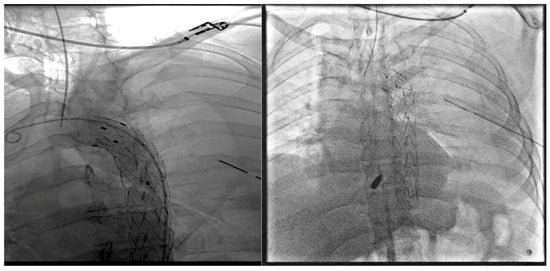

Multimodal Management of a Descending Aorta Injury with Penetrating Chest Trauma: A Case Report

2. Case Presentation